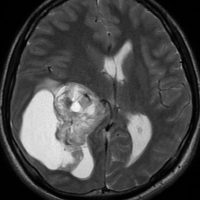

- MRIでは,脳室内に突出する境界明瞭な腫瘍です

- MRI T1強調画像では低信号に,T2強調画像では高信号に描出され,ガドリニウムで増強されます

- 腫瘍内部の信号強度は,石灰化や嚢胞形成,腫瘍内出血,壊死の混在により不均一になることの方がむしろ多いです

第4脳室床に発生した典型的な上衣腫 EPN-PFA の画像です。水頭症になって,頭痛と嘔吐,意識障害で発症しました。典型的なMRI画像と病理所見です。MRIでは第4脳室からマジャンディー孔を越えて脊髄背側まで長く腫瘍が伸びています。腫瘍内部に小さなのう胞が複数みられます。病理像では,血管周囲に細胞核がない無核野が認められます。血管周囲に伸びた繊細な単極性突起が集まった領域です。これは,血管周囲偽ロゼット perivascular pseudorosette という上衣腫に特徴的な病理所見です。